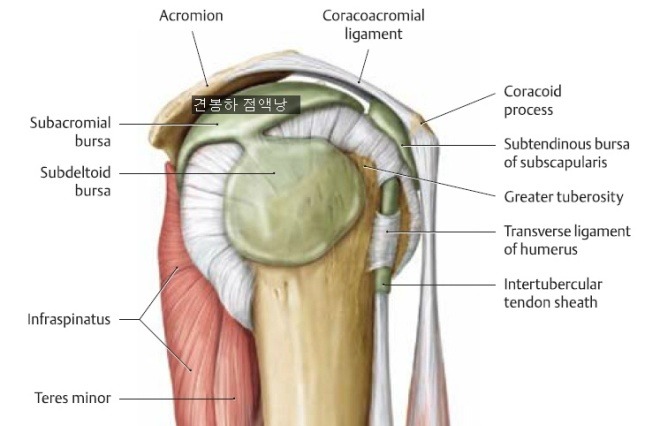

. 견봉하 점액낭염(subacromial bursitis)

- 견봉하 점액낭염이 발생하면 어깨 외전할때 통증이 발생하고, 점액낭 아래부위에서 무름징후가 관찰됨

원인은 friction heat

극상근 위에 있고 삼각근 아래에 있다. 견봉아래에 껴 있다.

초기 30도 극상근이 작동하고 그 후 삼각근이 작동. 반복하는 환경속에서 마찰열이 발생

견봉하에서 구조적으로 임핀지, 씹힌다. 다른 점액낭과 다르게 무지무지하게 아프다. 통각 심하게 느낀다. 밤에 아파 응급실 가기도 한다.

극상근건염은 통증이 별로 없다. 혈관이 없다. 신경이 없다.

견봉하 점액낭 그림보다 훨씬 큼

- 회전근개는 극상근, 극하근, 소원근 대원근, 견갑하근의 건으로 이루어짐.

- 회전근개는 gh joint를 안정화시키고, 상완골두의 과도한 상방움직임을 제한

- 극상근은 견갑골의 supraspinous fossa에서 기시하여 상완골의 대결절에 종지.

- 극상근은 견봉하 점액낭때문에 견봉, 견봉오훼인대, 삼각근과 분리되어 있다.

- 극상근과 삼각근 중앙부는 어깨의 주요 외전근육. 초기 외전시 극상근이 작용

- 견갑하근은 견갑골의 늑골면에서 기시하여 상완골 앞면에 종지, 견갑하근 아래에 견갑하 점액낭이 존재

- 견갑하근은 어깨의 내회전과 내전을 담당.